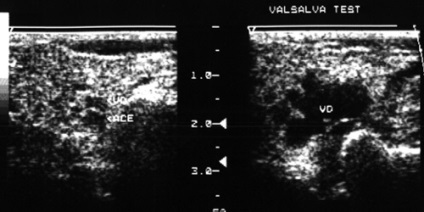

Így a betegség folyamatában lehet vonni csak vaszkuláris vagy perifériák - kapillárisok, vagy csak nagyobb hajók arteriovénás kommunikációs képződése (anasztomózisok, sipolyok), esetleg ezek kombinációja lehetőségeket. Elváltozásoktól csak lokalizálható a vénás oldalán a vaszkuláris ágy, az ilyen variáns lézió jelöljük távú „vénás diszplázia” (ábra. 32).

Érsérülések lehetnek diffúz terjedésének lágy szövet vagy egyértelműen elhatárolt, valamint amelynek a jellemzői az hemodinamika (ábra. 33).

Mindezek a tényezők teszi szükségessé az egyén megközelítése a választott módszer és taktika a kezelést. Ultrahangos vizsgálat, amely lehetővé teszi, hogy azonosítsa azokat a morfológiai és a hemodinamikai paraméterek érrendszeri elváltozások az arcon és a nyakon, egy hatékony módszer a diagnózis.